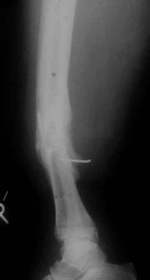

| Die Pseudarthrose war bei der Operation noch so beweglich, daß

sie geschlossen achsengerecht reponiert werden und mit einem unaufgebohrten

V-Nagel stabilisiert werden konnte. Um bei der Belastung die für

die Frakturheilung notwendigen Mikrobewegungen zu bekommen, wurde

das Wadenbein durchtrennt. (Wadenbeinosteotomie) |